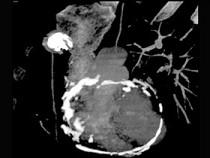

问题 男性45岁,心悸气促乏力,下肢肿胀半年余,曾患肺结核,胸部CT扫描如图所示,请选择正确的选项为 ( )

选项 A、X线、CT为常用检查方法 B、MRI显示增厚的心包较X线、CT优越,但是对心包钙化不敏感 C、心包钙化显著时也可称之为“盔甲心” D、心包钙化多见于结核 E、考虑为缩窄性心包炎 一、多项选择题

答案 ABCDE